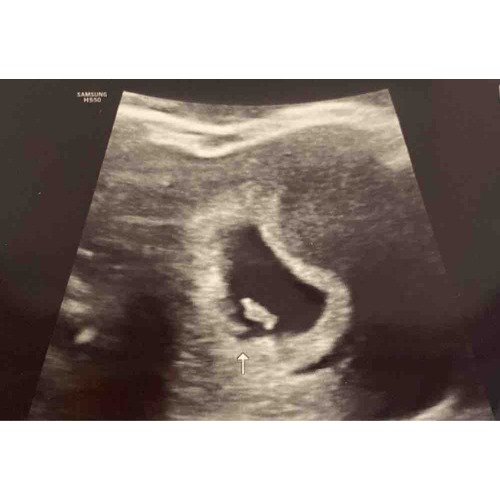

6 weken en 3 dagen! Ook kloppend hartje. Komt idd ook wel overeen 🥰